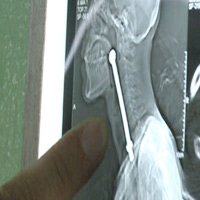

Chú cá dài khoảng 16 cm mắc kẹt trong cổ họng cậu thanh niên.

Tại đây, các bác sĩ đã thực hiện một ca phẫu thuật khẩn cấp để lấy con cá ra ngoài. Sau 5 giờ, họ đã lấy được chú cá dài 16 cm ra ngoài cổ họng bệnh nhân.